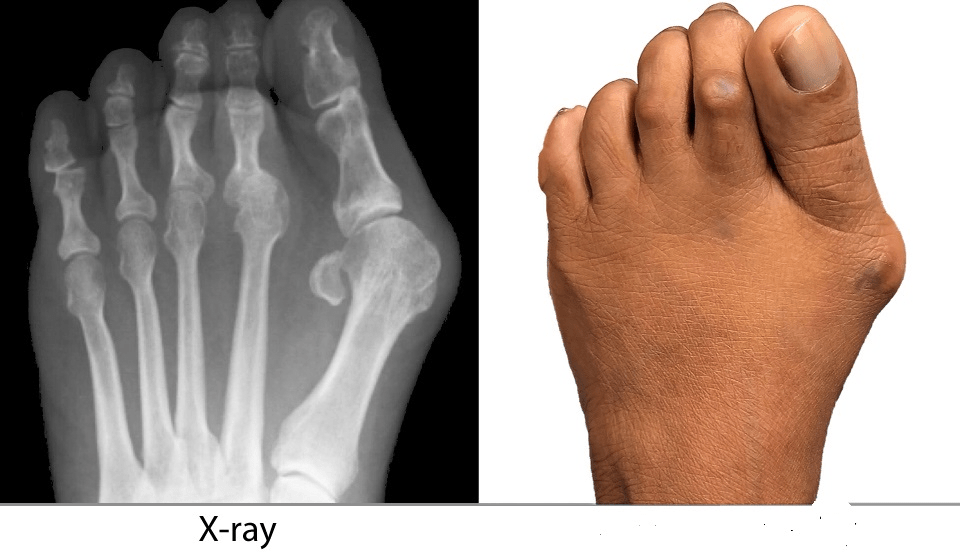

Tenderness, swelling, and enlargement of joint of the 1st Metatarsophalangeal joint. As inflammation continues, angulation increases causing painful ambulation. Tendinitis in great toe flexors may develop. Looking for the medical term and there are two words in the name.

Hallux Valgus